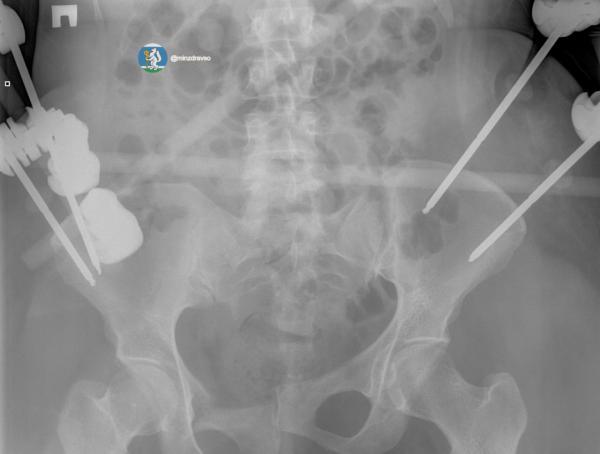

По данным министерства здравоохранения Свердловской области, благодаря вовремя прибывшей бригаде «скорой» удалось сохранить драгоценные минуты и доставить женщину в больницу, где в течение первых 15 минут были проведены все необходимые исследования. Врачи диагностировали тяжелую политравму, включающую закрытую черепно-мозговую травму, ушиб головного мозга, повреждение челюстно-лицевых костей, ребер, двусторонний пневмоторакс, оскольчатый перелом правой ключицы и раздробленные кости таза.

«Крайне тяжелое повреждение таза представляло высокий риск массивной кровопотери, поэтому борьба за жизнь пациентки началась с немедленной стабилизации ее состояния. Медики качественно скрепили отломки костей всех поврежденных сегментов костей и таза аппаратами внешней фиксации.   Профессионализм и опыт врачей, их высочайшая квалификация и плановое совершенствование экстренной медицинской помощи в Свердловской области подарили пациентке получить второй день рождения», — отметили в минздраве региона.

Аппараты внешней фиксации помогли пациентке минимизировали последствия травм, тем самым сохранив качество жизни. Сейчас женщина уже дома с семьей.